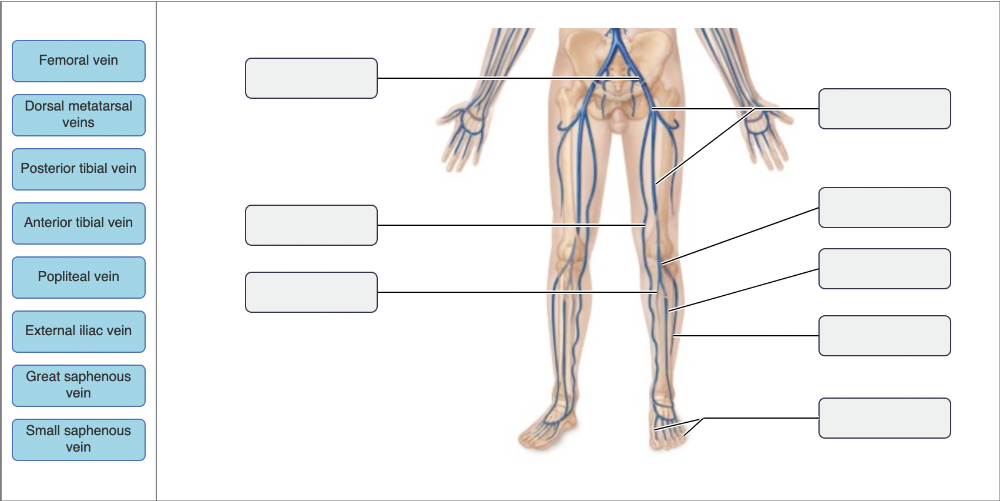

Drag the appropriate labels to their respective targets.

Name the vein at A.

- femoral vein

- small saphenous vein

- fibular vein

- external iliac vein

femoral vein

Ex.

The femoral vein is the largest vein draining the lower extremity. It unites with other veins to form the external iliac vein.